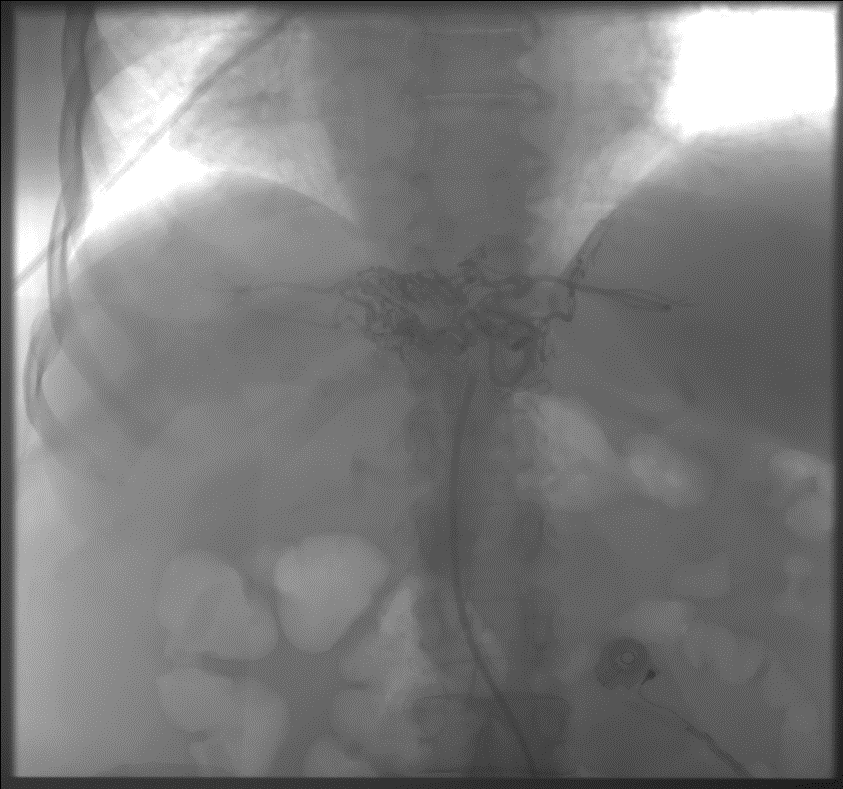

Рентгенэндоваскулярные вмешательства

эндопротезироваскулярная остановка кровотечения при мальформации желудочных сосудов